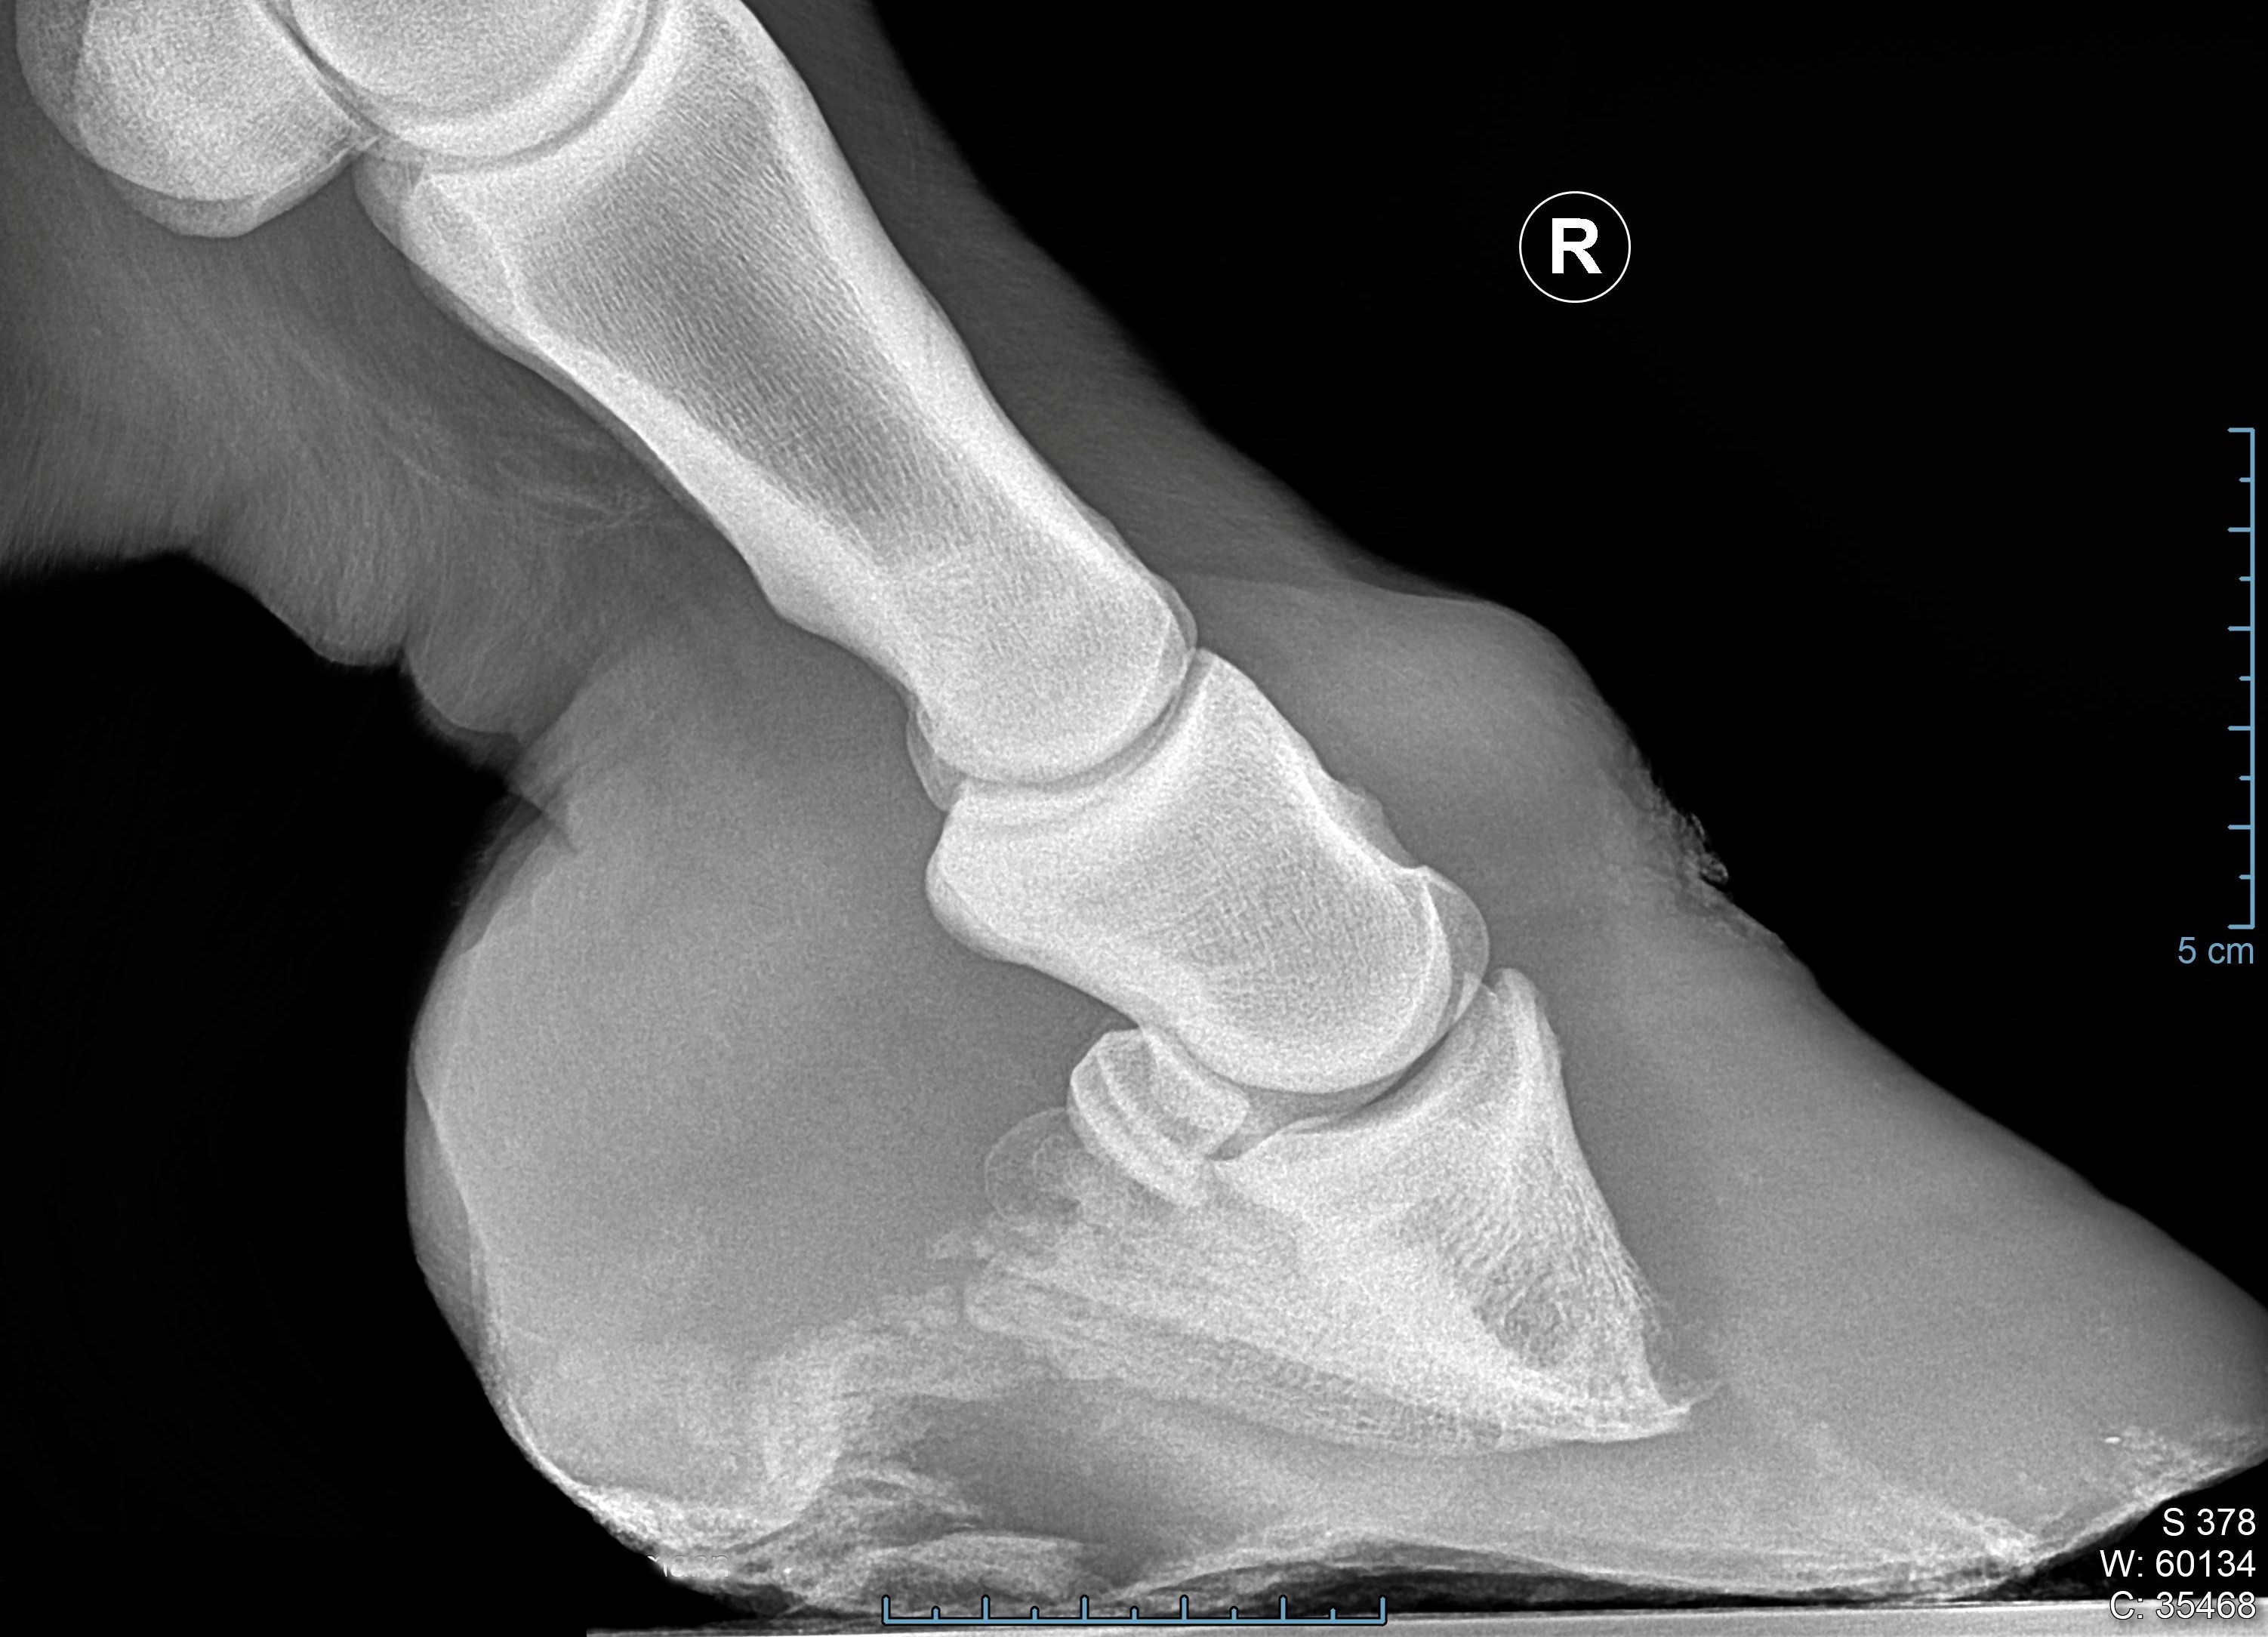

Fallbeispiele

Gute Hufbearbeitung passt zum Gebäude des Pferdes und ist daher individuell